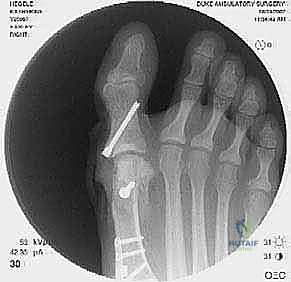

2. التصوير الشعاعي المتقدم

- الأشعة السينية مع تحمل الوزن (Weight-bearing X-rays): صور من الأمام، الجانب، والزوايا المائلة لتقييم زوايا العظام تحت تأثير وزن الجسم.

- تصوير السمسمانيات (Sesamoid view): لمعرفة ما إذا كانت العظام السمسمانية قد خُلعت من مكانها.

- يتم تحديد مواقع المسامير أو الشرائح المعدنية من الجراحة السابقة وإزالتها (Hardware Removal). قد تكون هذه الخطوة صعبة إذا نما العظم فوق المسامير.